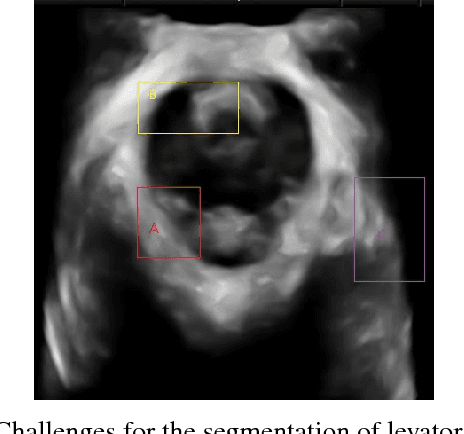

Abstract:In this paper, a multi-scale framework with local region based active contour and boundary shape similarity constraint is proposed for the segmentation of levator hiatus in ultrasound images. In this paper, we proposed a multiscale active contour framework to segment levator hiatus ultrasound images by combining the local region information and boundary shape similarity constraint. In order to get more precisely initializations and reduce the computational cost, Gaussian pyramid method is used to decompose the image into coarse-to-fine scales. A localized region active contour model is firstly performed on the coarsest scale image to get a rough contour of the levator hiatus, then the segmentation result on the coarse scale is interpolated into the finer scale image as the initialization. The boundary shape similarity between different scales is incorporate into the local region based active contour model so that the result from coarse scale can guide the contour evolution at finer scale. By incorporating the multi-scale and boundary shape similarity, the proposed method can precisely locate the levator hiatus boundaries despite various ultrasound image artifacts. With a data set of 90 levator hiatus ultrasound images, the efficiency and accuracy of the proposed method are validated by quantitative and qualitative evaluations (TP, FP, Js) and comparison with other two state-of-art active contour segmentation methods (C-V model, DRLSE model).